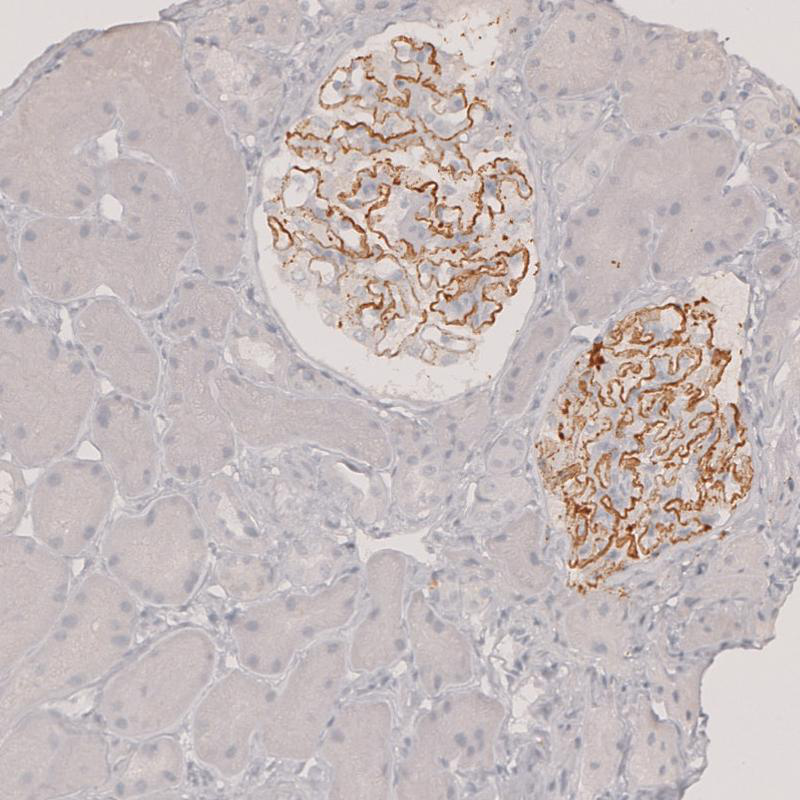

Immunohistochemical staining of human Kidney shows strong membranous positivity in cells in glomeruli.